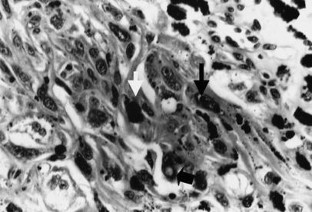

Fig. 3